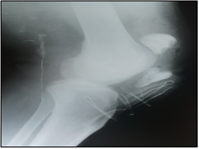

After a decline of six months (Figure 1), we identified one (01) case of pseudarthrosis or 5.88% and one (01) case of patellofemoral osteoarthritis or 5.88%.

(a) (b) (c) (d)

Figure 1. (a) Fracture of the patella, Duparc type II; (b and c) osteosynthesis by cerclage; (d) knee flexion at six months.